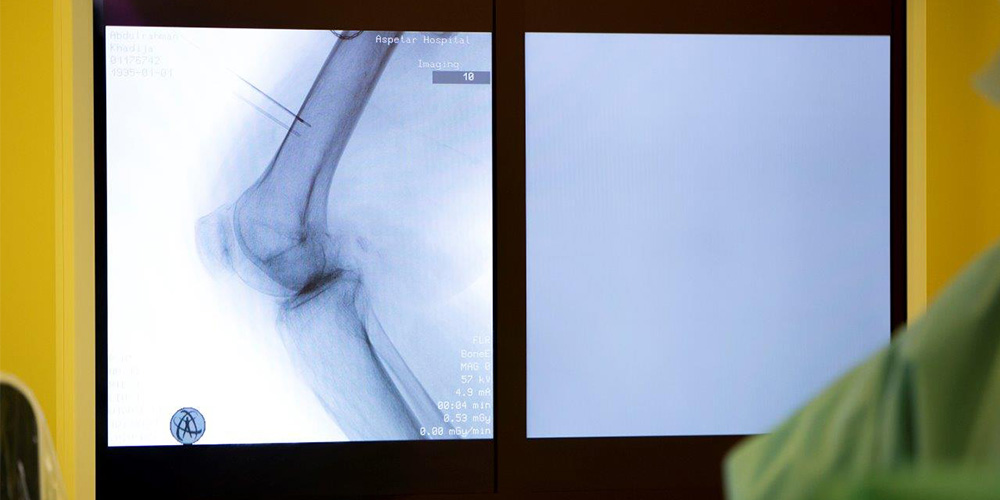

This technique consists of the use of a needle probe attached to a particular medical device- the RF Generator. The probe is placed under imaging guidance at the target nerve tissue followed by nerve testing before the application of the electromagnetic field. This results in a special type of non-permanent “lesion” of the nerve fibres allowing very good control of difficult pain conditions. RF lesioning procedures typically require from 15 to 45 minutes”.

Where RF lesioning is designed to help people, who suffer from chronic pain. Aspetar experts use C-RF for areas including the knee, shoulder, hip, and the spine. “It is very important to be aware that no one technique fits all diseases! Therefore, the patient will have to be well-examined, the medical condition investigated by imaging such as X-Ray, US or/ and MRI before making the decision to perform this technique or another procedure as needed” added Dr Yasin.